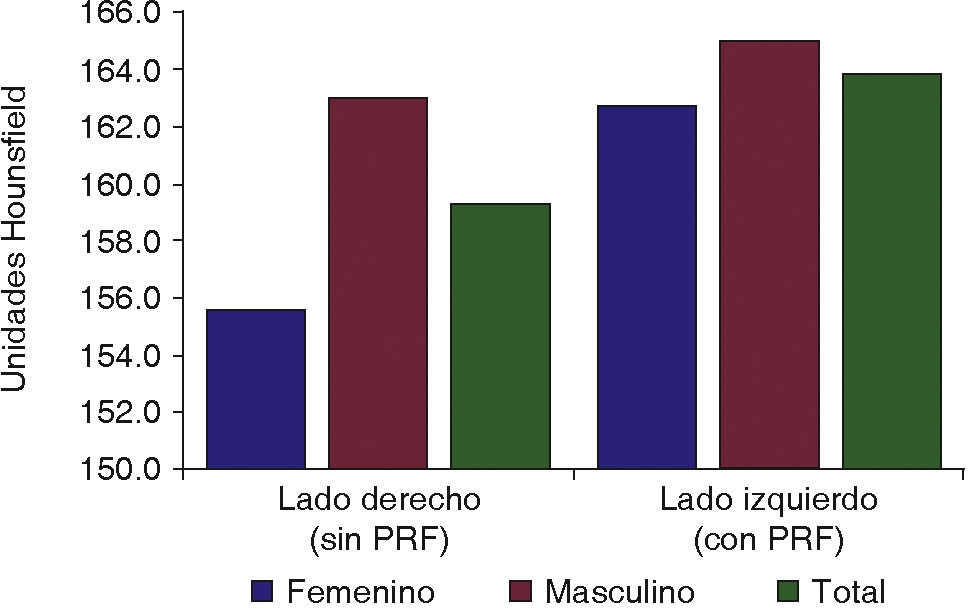

De los 30 pacientes incluidos en el estudio, 15 fueron del sexo femenino y 15 del sexo masculino. Fueron agrupados por edad, 8 pacientes de 16 a 19 años, 15 pacientes de 20 a 23 años, y 7 pacientes de 24 a 27 años (Figura 4). Se catalogaron por dificultad de extracción según la clasificación de Pederson17 en leve, moderada y muy compleja, con resultados de 7 leves, 22 moderadas y una muy compleja en el lado derecho y 8 leves, 20 moderadas y 2 muy complejas en el lado izquierdo (Figura 5).

La cicatrización del tejido óseo tuvo mejor puntuación en el lado experimental con valores de densidad de 163.9 HU comparado con el lado control de 159.3 HU (Figura 7). La prueba t de Student dio un resultado de p = 0.015. Con relación al sexo y edad no se obtuvieron diferencias (Cuadro I). De acuerdo con la propuesta de criterios y escala de puntuaciones de Pederson, con relación a la dificultad de extracción, los mejores resultados se obtuvieron para los grupos de leve complejidad de extracción (Figura 8).

De la misma manera que en el tejido blando, los datos obtenidos sobre cicatrización de tejido óseo, fueron distribuidos por género y edad. En el primer grupo, el sexo masculino tuvo mejores valores medios, tanto sin y con el uso de PRF, estos valores fueron de 163.0 HU y 165.0 HU, respectivamente, comparado con el sexo femenino teniendo sin el uso de PRF un valor medio de 155.6 HU y de 162.7 HU con el uso de PRF.

En el estudio de Célio-Mariano,19 los resultados fueron similares, el sexo masculino tuvo valores medios más altos que el sexo femenino, tanto en el grupo de control, como en el grupo experimental.

La edad fue distribuida en tres grupos, de forma comparativa en la cicatrización de tejido óseo, los mejores valores medios se observaron para los grupos etarios del grupo experimental que para el grupo de control, y en cada caso el grupo de 20 a 23 años obtuvo el mejor valor.

El estudio demostró que la cicatrización de tejido blando y tejido óseo mejora con el uso de PRF, afirmando de esta manera su efectividad. Analizando por el grupo de edad, el de 20 a 23 años presentó mejor cicatrización de tejido óseo, comparado con el de 16 a 19 años que presentó el mejor resultado en cicatrización de tejido blando. Con relación al sexo masculino y femenino presentó mejor cicatrización el sexo masculino. Por último con respecto a la dificultad de extracción del tercer molar, no se vio influenciada la cicatrización en valores significativos, tanto en casos complejos, de mediana complejidad o en los que la cirugía se tornó rápida y fácil.